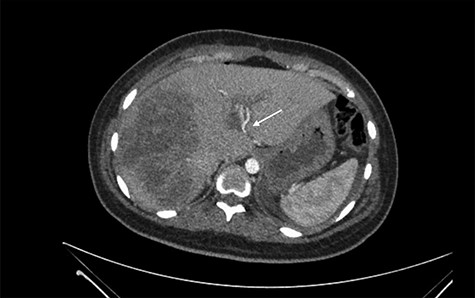

She was referred to our center on postoperative Day 4 due to progressive jaundice and encephalopathy. A triphasic contrast-enhanced abdominal computed tomography (CT) was done revealing a right liver lobe infarct, absence of the right and left hepatic arteries (Fig. 1), presence of an accessory left hepatic artery from the left gastric artery (Fig. 2) and right portal vein thrombosis with extension to the main portal vein (Fig. 3).

Accessory left hepatic artery (white arrow) on the arterial phase of the triphasic contrast-enhanced abdominal CT.

Main portal vein thrombosis (white arrow) on portal phase of the triphasic contrast-enhanced abdominal CT.